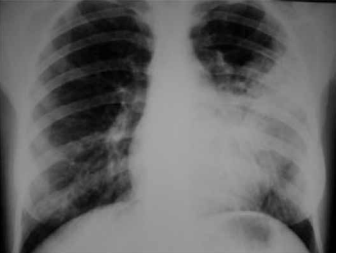

Mulher de 33 anos de idade refere febre, dispneia e dor torácica à esquerda há 3 dias. Nega tabagismo, etilismo ou patologias prévias. Exame físico: PA: 110 x 70 mmHg, FC: 96 bpm, FR: 18 ipm, T: 38,9 ºC e saturação arterial de O2: 94%; cardiovascular: normal; pulmão: crepitações em 2/3 inferior do hemitórax esquerdo. Radiografia realizada é mostrada a seguir.

O tratamento antimicrobiano inicial correto é